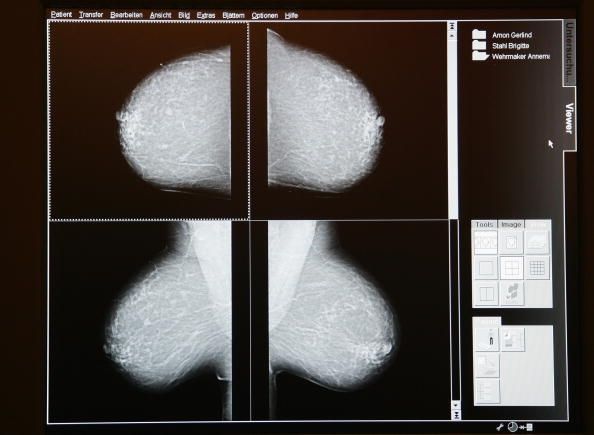

Según una encuesta, las mujeres que tienen cáncer en una mama consideran tener ambos senos removidos porque se preocupan por el desarrollo de cáncer en su otro seno. Alrededor de la mitad de estas mujeres consideran la mastectomía profiláctica de su otro pecho, incluso si no tienen mutaciones genéticas que predicen un segundo cáncer.

En la encuesta participaron 117 mujeres que estaban siendo tratados en la Universidad del Centro Oncológico MD Anderson de Texas en Houston. Todos tenían cáncer de mama en estadio temprano en un seno y fueron encuestados antes de su primera consulta de cirugía. También habían sido objeto de análisis genético que demostró que no tenían la mutación gen BRCA1, lo que aumentaría la probabilidad de que iban a desarrollar un segundo cáncer de mama.